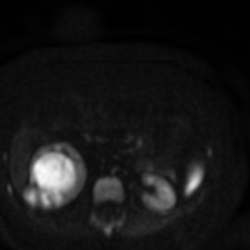

МРТ без контраста , несколько снимков прикрепляю.